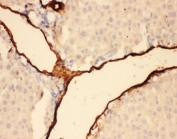

IHC-P testing of rat liver tissue. HIER: steamed with pH6 citrate buffer.